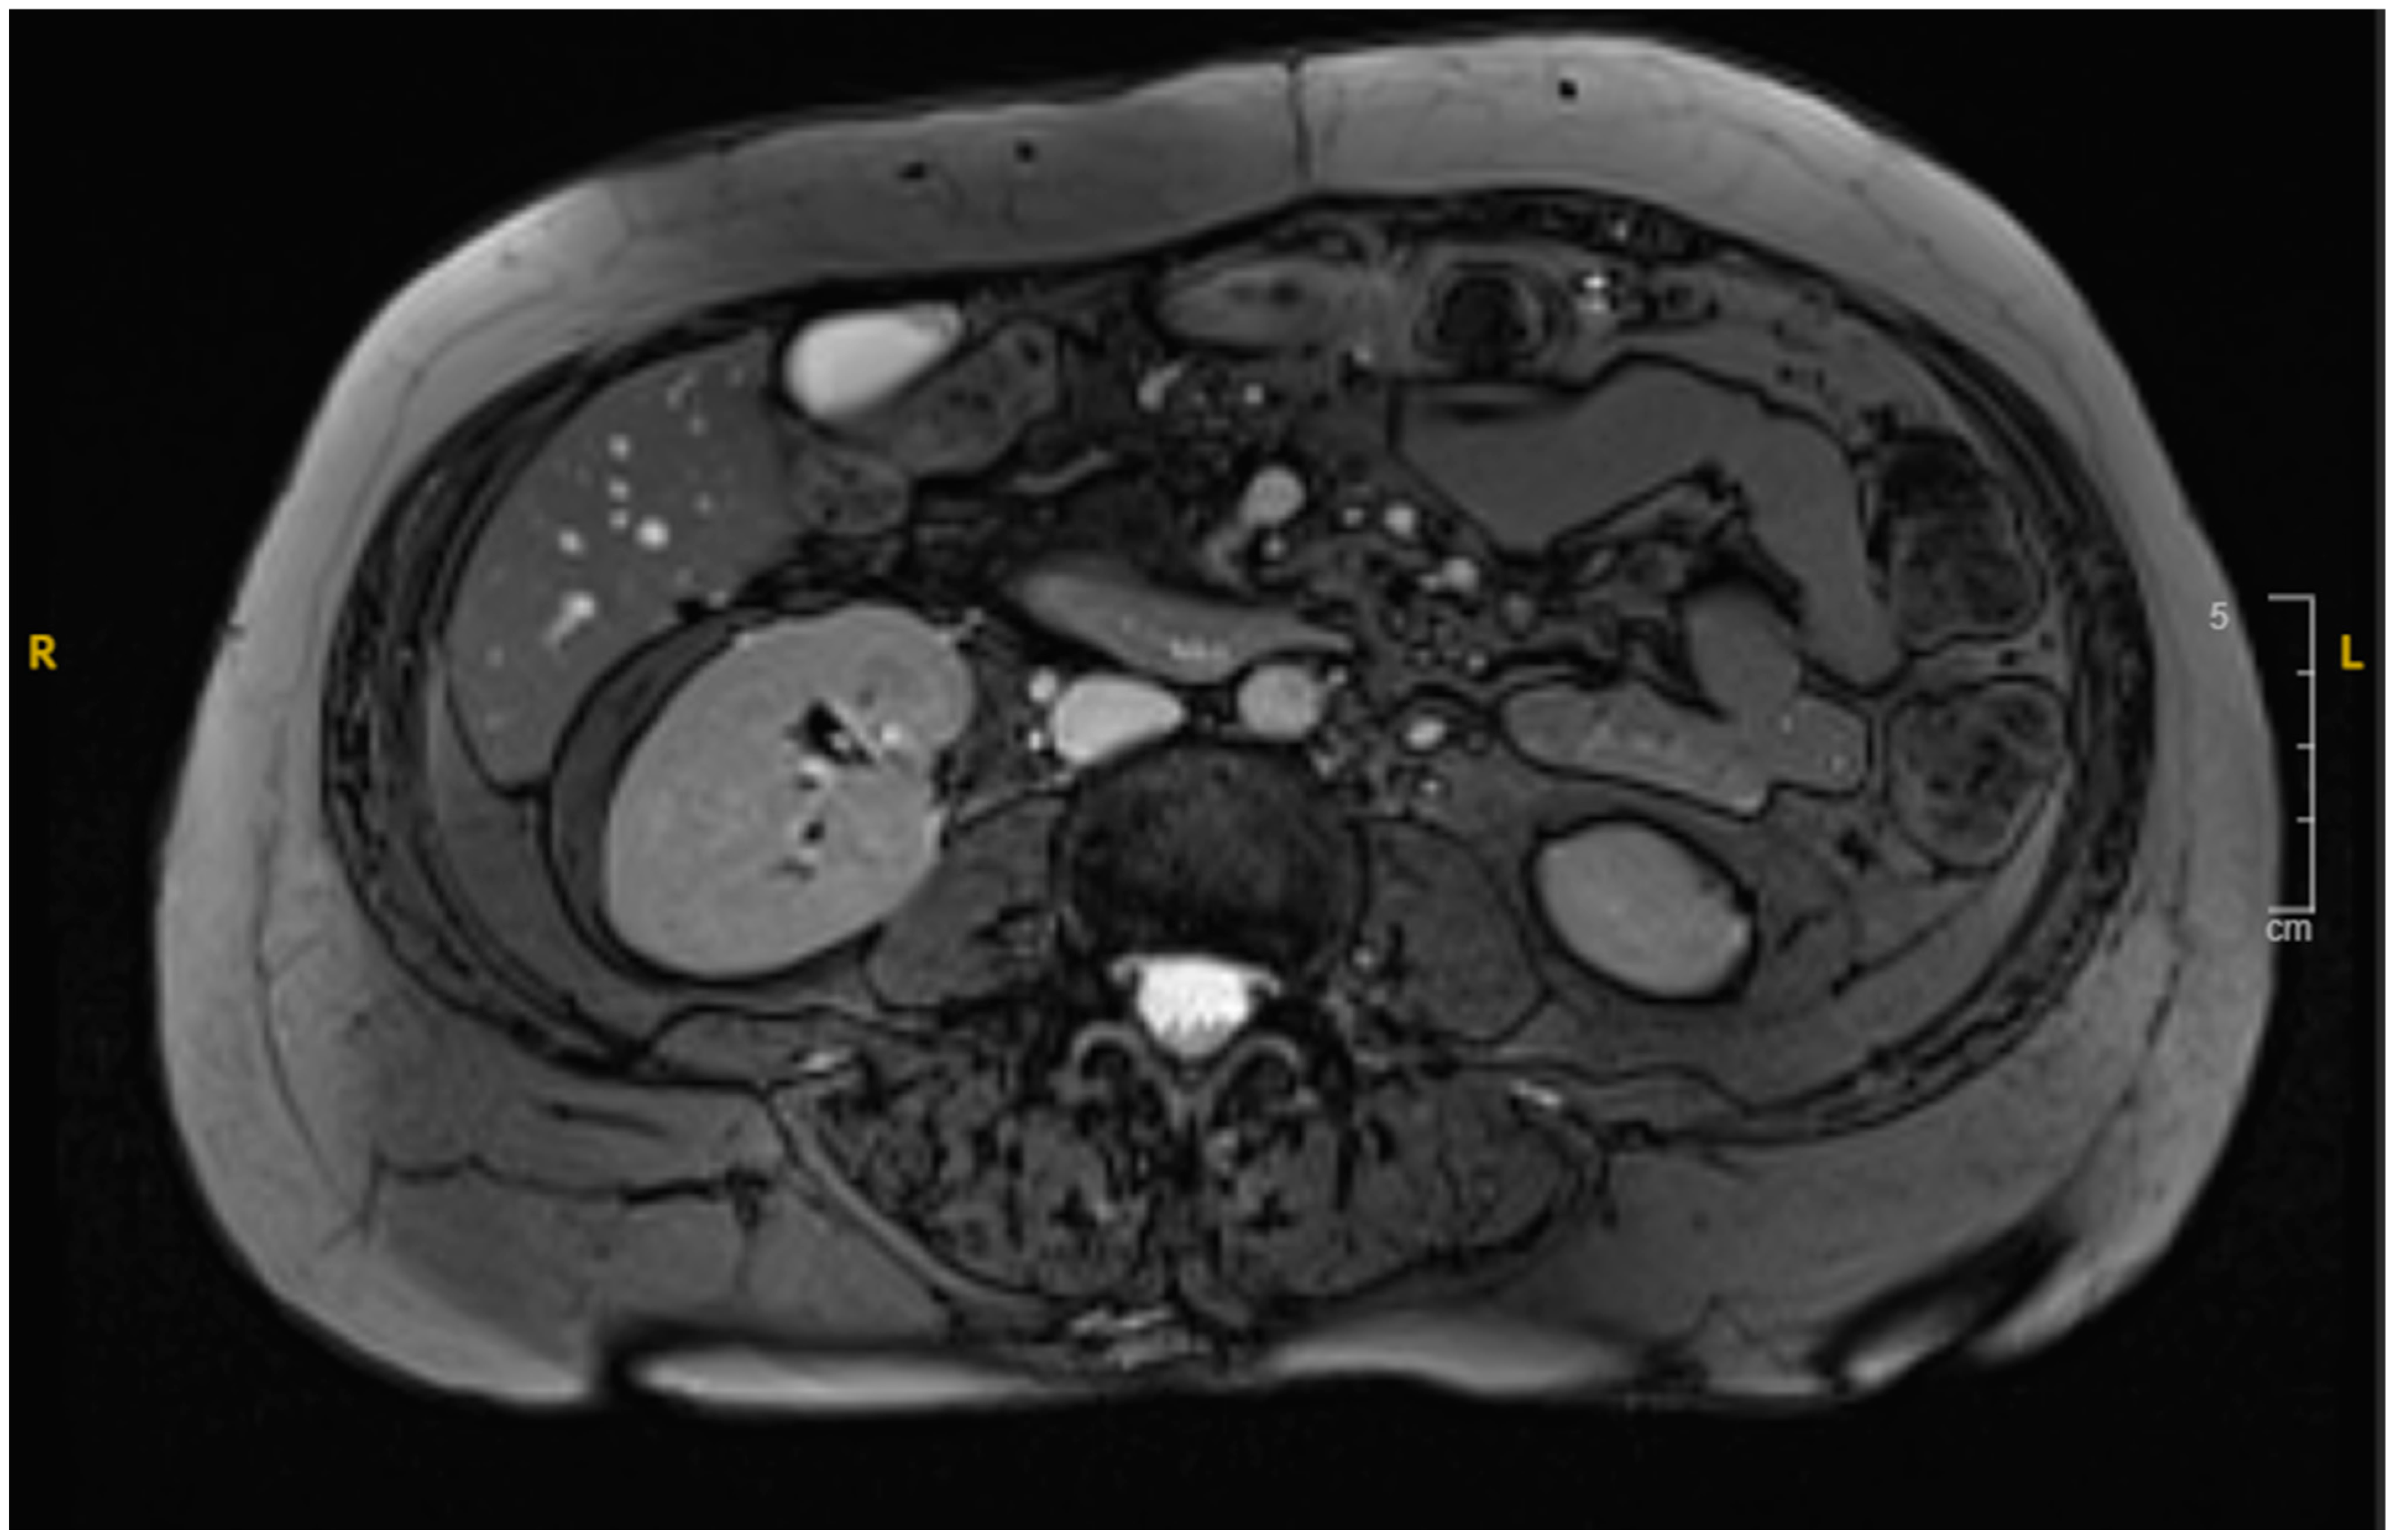

The patient showed significant improvement with conservative management and was discharged after three weeks, with a scheduled follow-up in outpatient care. A surveillance scan with IV contrast indicated complete resolution of the hematoma (Figure 4). The patient remained asymptomatic and was able to resume normal activities. A timeline detailing the patient’s diagnosis and treatment history is provided in (Figure 5).

Figure 4. MRI revealing resolution of the duodenal hematoma.